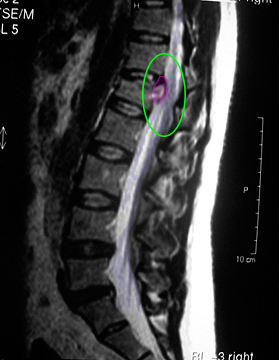

Κήλη θωρακικού μεσοσπονδύλιου δίσκου με πίεση στην τελική μοίρα του νωτιαίου μυελoύ

Κήλη θωρακικού μεσοσπονδύλιου δίσκου με πίεση στην τελική μοίρα του νωτιαίου μυελoύ